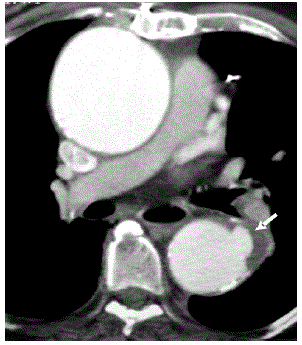

Paciente masculino, com doença aterosclerótica sabida associada a aneurisma da aorta ascendente dá entrada na emergência com dor torácica importante e interescapular.

Baseado na imagem disponibilizada, qual o seu diagnóstico?